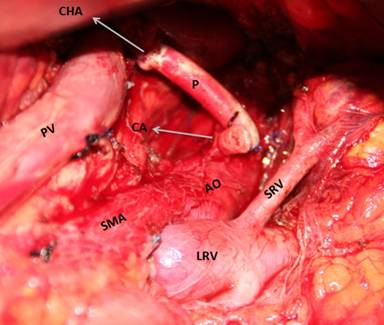

End to end anastomosis from common hepatic artery and celiac axis resulted technically impossible due to the distance between both ends. Besides, at ultrasound we found an atheromatous plaque at the origin of the celiac axis. Therefore, we performed an end to end anastomosis with a prosthetic graft (8 mm Dacron graft, 5-0 prolene suture) from common hepatic artery directly to the aorta, over the celiac axis, where no atheromatous plaque was found at ultrasound (Figure 2). When the vascular clamp to the aorta was released, the following Doppler showed an acceptable flow thought the distal hepatic artery. One round 19F Blake abdominal drain was left in place.

Figure 2. Intraoperative view. AO: aorta; LRV: left renal vein; P: prosthesis; PV: portal vein; SRV: supra-renal vein |